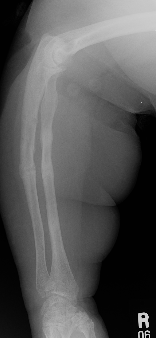

Bowing of the radius and ulna; multiple healing fractures; osteopenia

Bone Lesions Case 5 Additional Images

Rickets